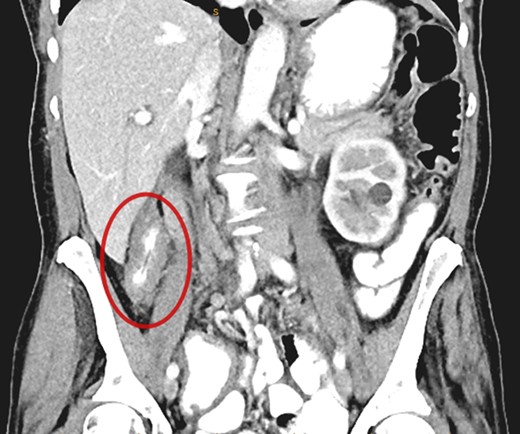

A CT abdomen/pelvis performed on the same day demonstrated contiguous bowel wall thickening from terminal ileum extending to distal ascending colon. There was no evidence of disease elsewhere; notably, there was no evidence of peritoneal disease or ascites.

Submucosal biopsies from ascending colon unexpectedly demonstrated metastatic carcinoma consistent with female genital tract origin—CK7 positive; CK20 negative; PAX-8/WT-1/ER/CA125 all positive. A PET/CT was performed on the basis of the histological findings, which demonstrated intense FDG-avidity in the known site of disease in the ascending colon (Figs 2 and 3), as well as a separate focus of increased metabolism in the left pelvic side-wall (Fig. 4), which was presumed to represent an ovarian primary. There was no evidence of nodal or peritoneal disease, however, note was made of mild bilateral hydroureter without clear transition point. CA125 was 118 U/mL (Ref. range 0–35).